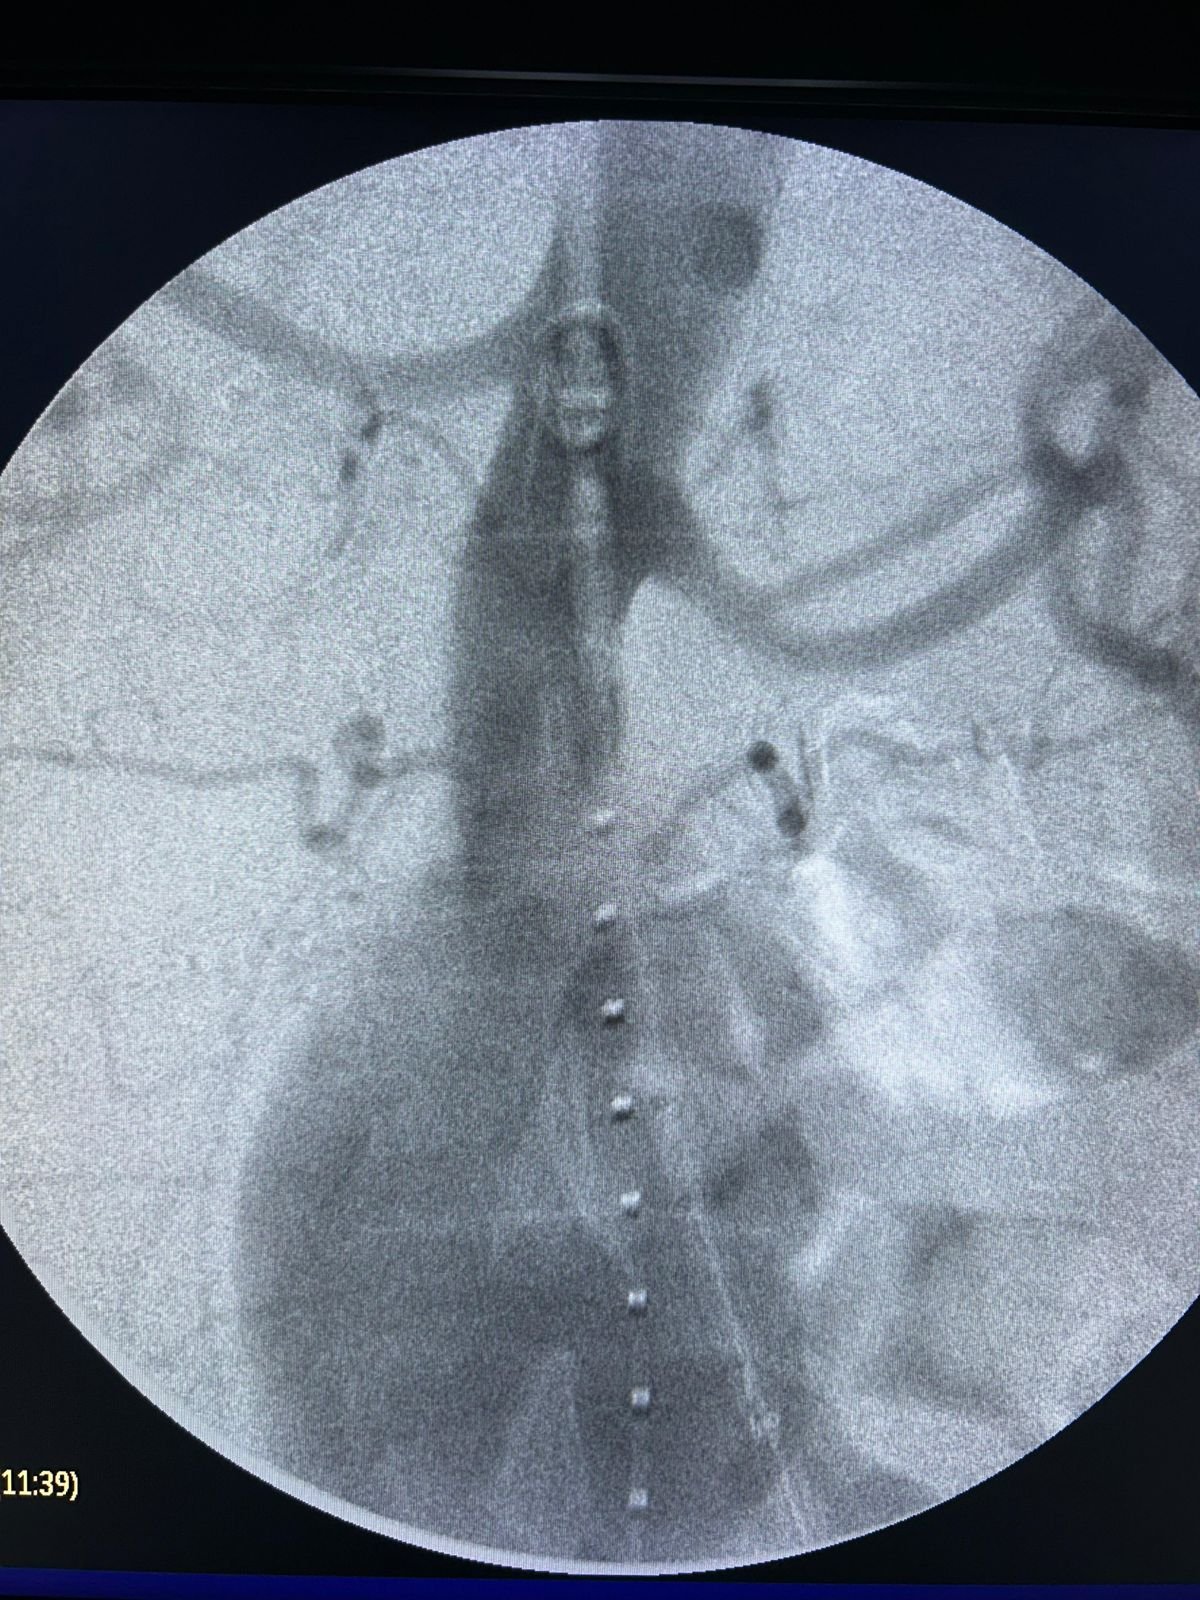

En Ecuador se realizó con éxito el primer procedimiento endovascular para el tratamiento combinado de Aneurisma de Aorta Abdominal (AAA) e ilíaco, utilizando la endoprótesis Minos™ Ultra Low Profile de MicroPort Endovastec, una solución avanzada diseñada para accesos vasculares complejos y anatomías desafiantes.

👨⚕ El paciente, un hombre de 66 años, presentaba un AAA de 74 mm y un aneurisma de Ilíaca Primitiva de 70 mm, con accesos finos y tortuosos y un cuello distal de aorta de 23 mm.

El abordaje incluyó:

Embolización de Hipogástrica derecha con coils

Implante de endoprótesis aorto-bi-ilíaca hasta la ilíaca externa derecha e ilíaca primitiva izquierda